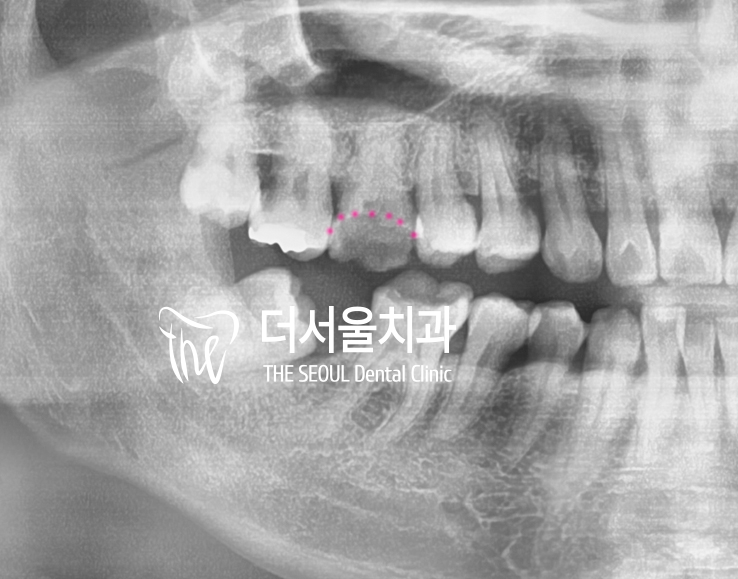

안녕하십니까, 박현준 원장입니다. 치아가 파절 된 범위에 따라서 발치를 해야 되느냐 또는 보존치료를 하느냐 결정이 됩니다. 여기서 환자의